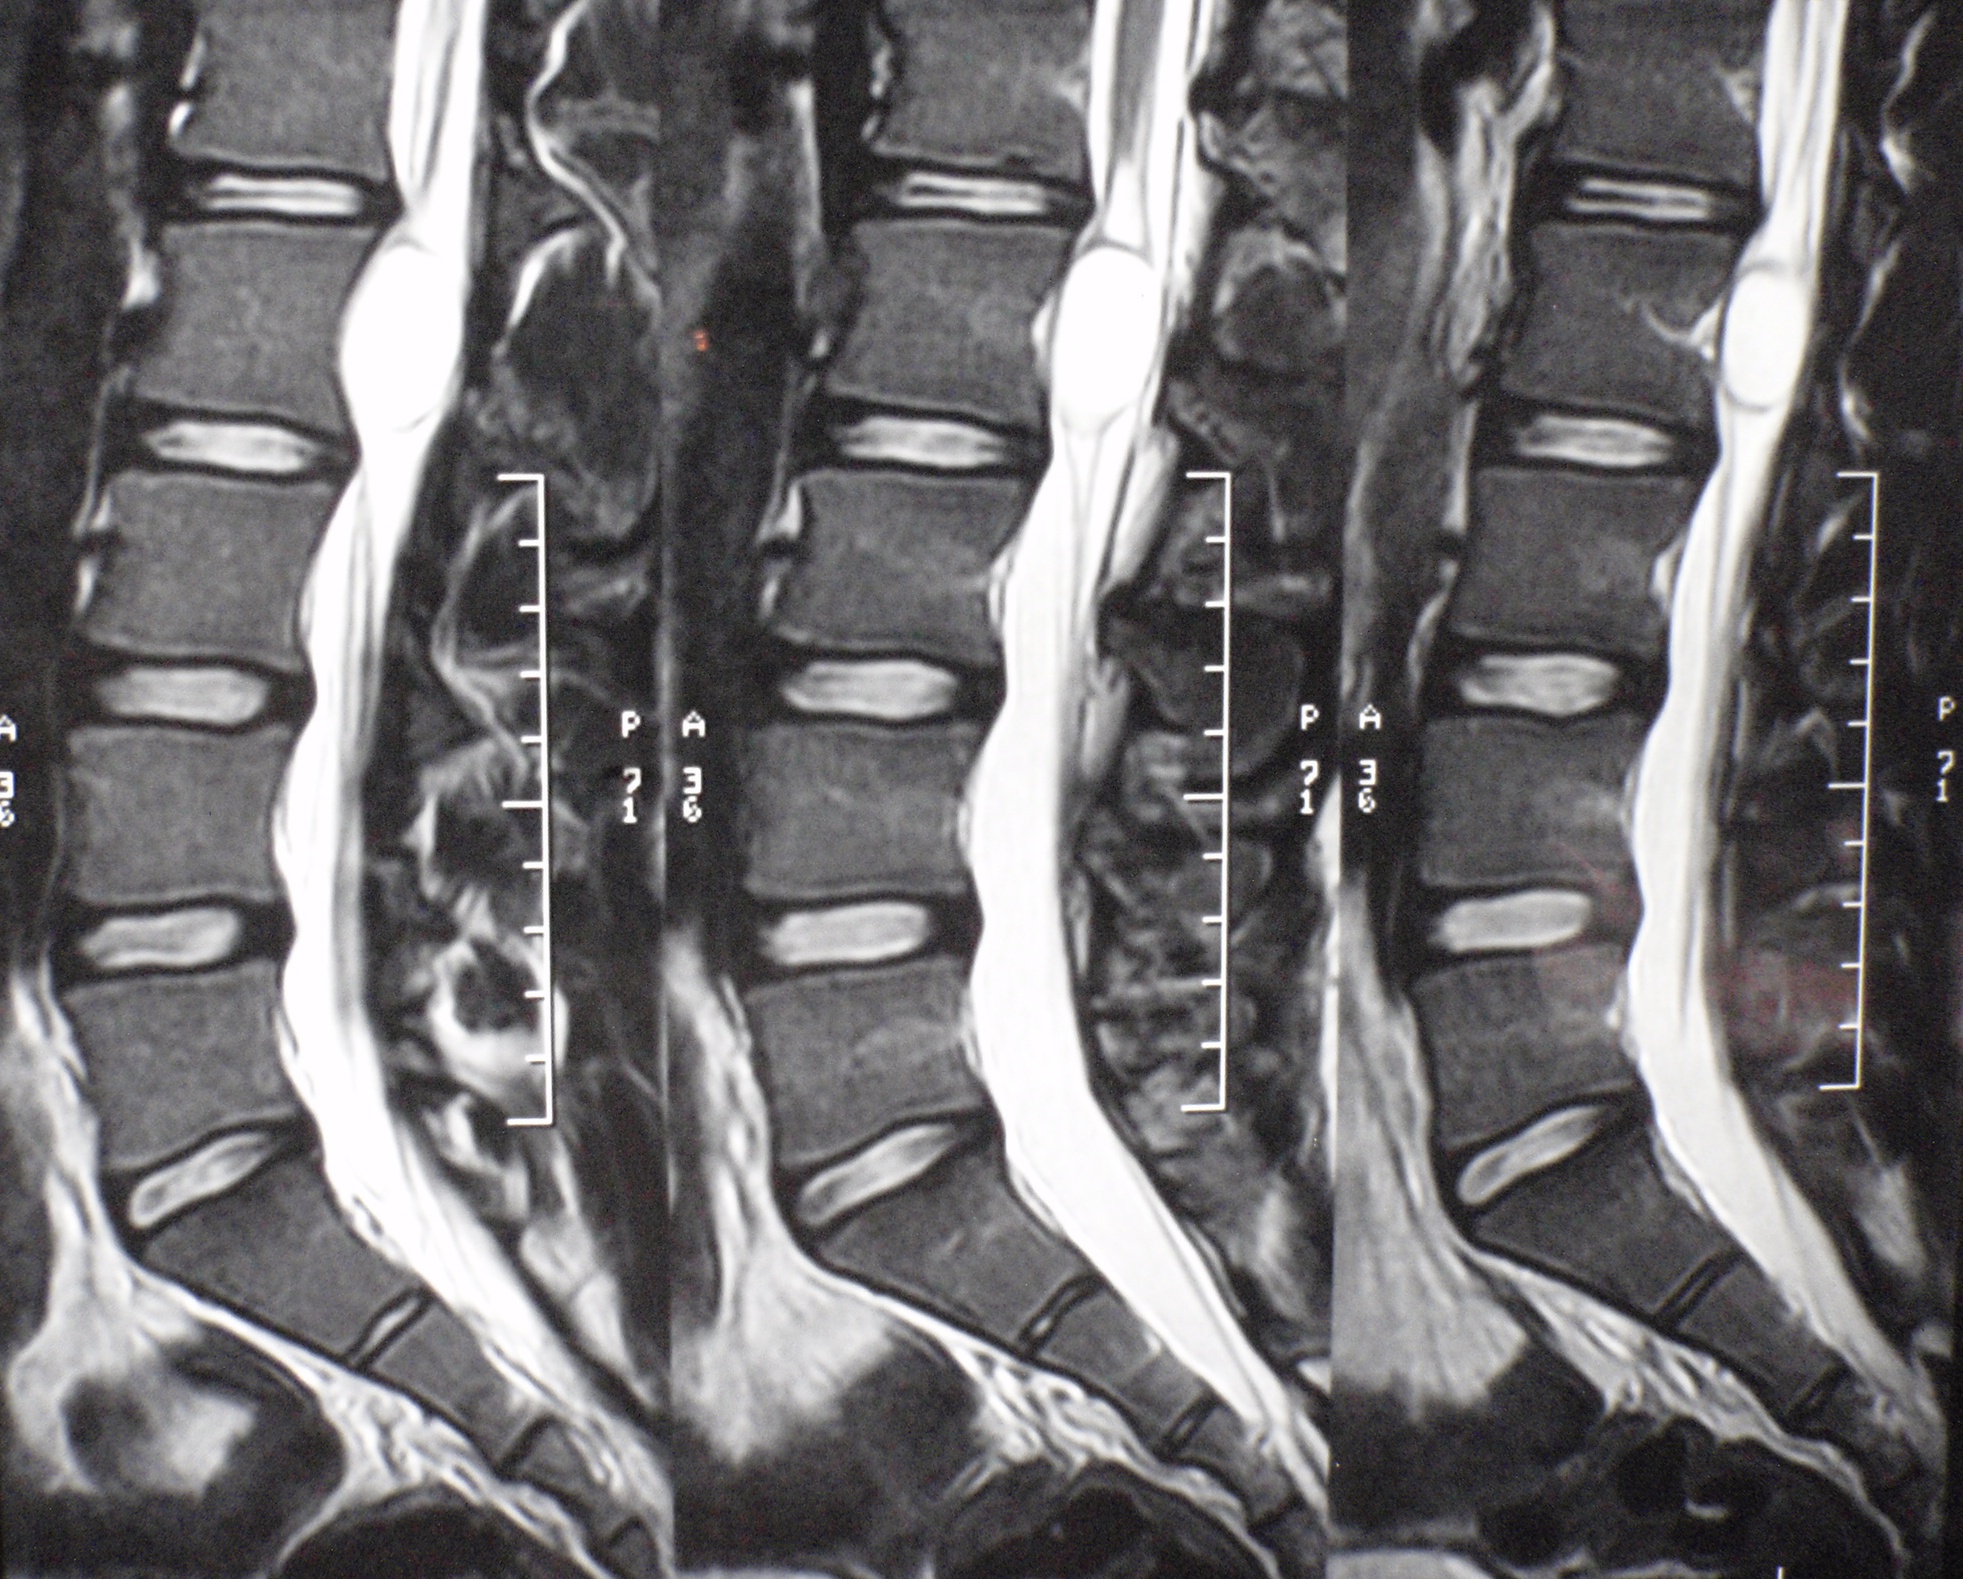

Quiste neuroentérico intradural. Reporte de un caso. [Intradural neurenteric cysts. Case report].